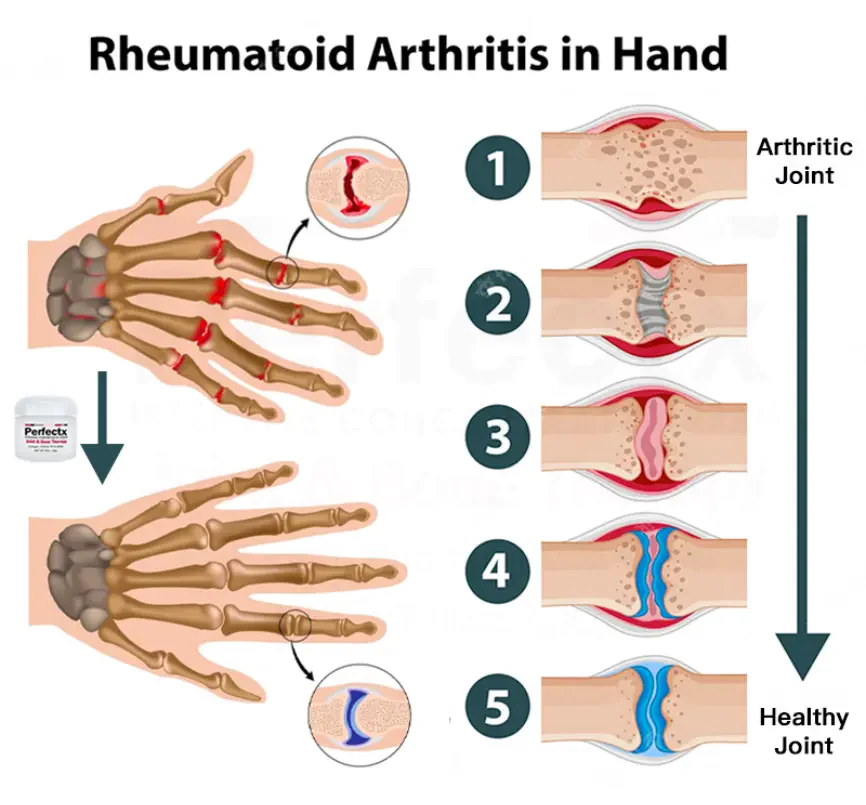

(u. a. Arthrose, rheumatoide Arthritis, Schleimbeutelentzündung, Sehnenentzündung, Osteoporose, Gicht, Karpaltunnelsyndrom, Bänderverstauchungen und -zerrungen, Ballenverformungen und Tennisarm).

Häufige orthopädische Gelenksymptome

Arthritis bezieht sich auf entzündliche Erkrankungen, die in den Gelenken und den umgebenden Geweben des menschlichen Körpers auftreten und durch Entzündung, Infektion, Degeneration, Trauma oder andere Faktoren verursacht werden, und kann in Dutzende von Arten unterteilt werden. Zu den klinischen Symptomen gehören Rötung, Schwellung, Hitze, Schmerzen, Funktionsstörungen und Verformungen der Gelenke, die zu einer Behinderung der Gelenke führen und die Lebensqualität der Patienten beeinträchtigen können.

Jennifer Betz: “Nachdem ich jahrelang unter rheumatoider Arthritis in meinen Händen gelitten habe, bin ich überglücklich, dass die Behandlung so einfach und unkompliziert ist. Es war eine große Erleichterung, einen wirksamen Weg zu finden, meine Krankheit zu behandeln, und es hat mir ein neues Gefühl der Hoffnung und Freiheit gegeben.”